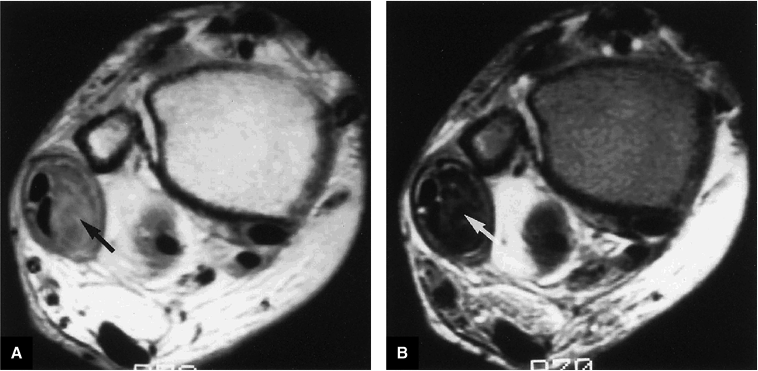

|